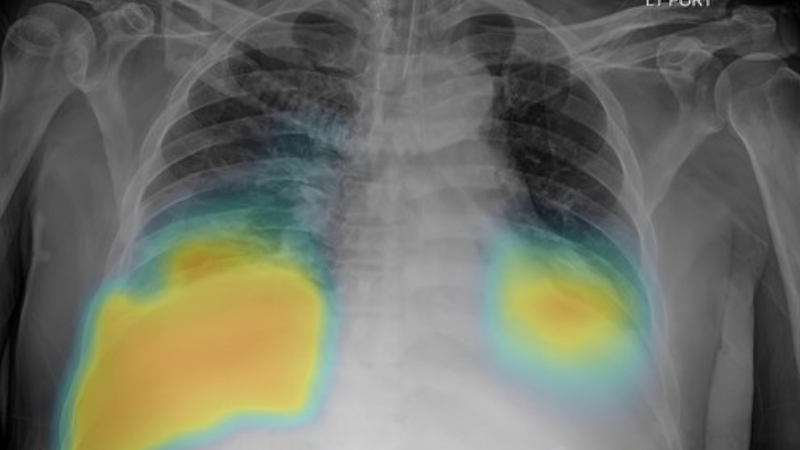

TB remains one of the world’s deadliest infectious diseases, requiring stronger diagnostic capacity and more resilient supply systems. Detecting TB early – particularly drug-resistant TB (DR-TB) – depends on reliable access to molecular diagnostics, imaging technologies, and laboratory consumables. Effective TB diagnostics supply chain management ensures these tools are available across health systems, helping countries expand screening and strengthen case detection.

TB diagnostics and drug-resistant TB detection